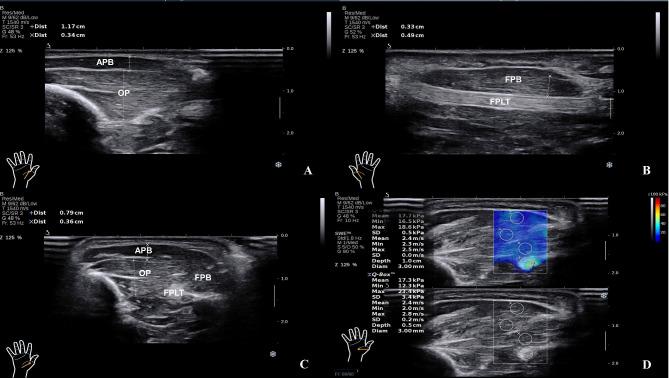

This study collected 60 patients diagnosed with hemiplegia after stroke from October 2021 to October 2022. Therapists used the Brunnstrom assessment (BA)scale to divide the patients into the stage. All the patients underwent the measurement of SWE examination of abductor pollicis brevis (APB), opponens pollicis (OP), flexor pollicis long tendon (FPLT), and flexor pollicis brevis (FPB) by two sonographers. The SWE change rate of four parts of the thenar area was calculated prospectively with the non-hemiplegic side as the reference, the function equation was established by the Bayes discriminant method, and the evaluation model was fitted according to the acquired training set data. Lastly, the model was verified by self-validation, cross-validation, and external data validation methods. The classification performance was evaluated regarding the area under the ROC curve (AUC), sensitivity, and specificity.

The median SWE values of the hemiplegic side of patients were lower than those of the non-hemiplegic side. According to the BA stage and SWE of APB, OP, FPLT, and FPB, our study established the Bayes discriminative model and validated it via self-validation and cross-validation methods. Then, the discriminant equation was used to validate 18 patients prospectively, the diagnostic coincidence rate was about 78.8%, and the misjudgment rate was approximately 21.2%. The AUC of the discriminant model for diagnosing BA stage I-VI was 0.928(95% CI: 0.839-1.0),0.858(95% CI: 0.748-0.969),1.0(95% CI: 1.0-1.0), 0.777(95% CI: 0.599-0.954),0.785(95% CI: 0.593-0.977) and 0.985(95% CI: 0.959-1.0), respectively.